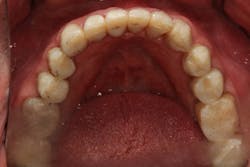

Founder Dr. Peter Dawson pioneered a systematic approach that allows any dentist to properly diagnose the root cause of wear issues. I knew that I could follow this approach to create a beautiful, highly functional, and long-lasting solution (figure 2).

Figure 2: After